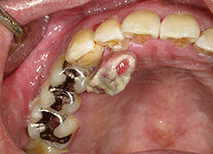

図❶ 初診時の口腔内写真

口腔内所見:32口蓋歯肉に、拇指頭大で有茎性、表面白色のびらんを伴う腫瘤を認めた(図❶)。硬結は触知しなかった。